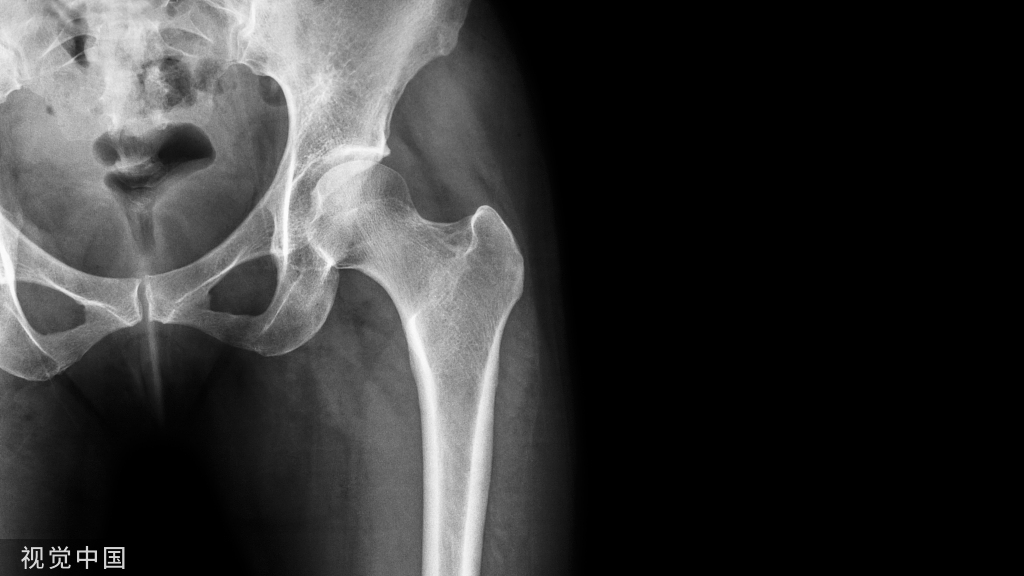

我们选择了一篇2023年6月发表的一篇骨科论文,主要对比了股骨远端粉碎性骨折的双钢板治疗相比于单钢板可以更好地预防术后内翻畸形。

论文摘要如下:Abstract 摘要Introduction 引言Varus collapse followed by osteosynthesis for distal femoral fractures with conventional implants has been well documented but is seldom mentioned in fractures managed with locking plates. The purpose of this study was to assess the incidence of varus collapse after treating complex supra-intercondylar fractures of the distal femur (AO type C3) using a Single Plate (SP) or Double Plate (DP) fixation technique.使用常规植入物治疗股骨远端骨折发生内翻塌陷的情况已有充分文献记载,但在使用锁定钢板治疗的骨折中很少提及。本研究的目的是评估使用单板 (SP) 或双板 (DP) 固定技术治疗股骨远端复杂髁间上骨折(AO C3 型)后内翻塌陷的发生率。

Materials and methods 材料与方法We retrospectively reviewed 357 patients with distal femoral fractures who were treated at our hospital between 2006 and 2017. After excluding cases of infection, malignancy, periprosthetic fracture, revision surgery, pediatric fracture, and extra-articular fracture, 54 patients were included in the study. All demographic data and radiological and clinical outcomes were reviewed and analyzed.我们回顾性研究了 2006 年至 2017 年间在我们医院接受治疗的 357 例股骨远端骨折患者。在排除感染、恶性肿瘤、假体周围骨折、翻修手术、小儿骨折和关节外骨折病例后,该研究纳入了 54 例患者。对所有人口统计学数据以及放射学和临床结局进行了审查和分析。

Results 结果There were 54 patients enrolled into this study with age from 15 to 85 years old (mean 41.6, SD = 19.9), and 32 of them were open fractures (59%). The patients were further divided into either an SP (n = 15) or a DP group (n = 39). Demographics, including age, sex, injury severity score, and open fracture type, were all compatible between the two groups. The overall nonunion rate was 25.9% (n = 14; 6 from the SP and 8 from the DP group; p = 0.175). The varus collapse rate was 9.3% (n = 5; 4 from the SP and 1 from the DP group (p = 0.018).本研究共有 54 名患者,年龄在 15 至 85 岁之间(平均 41.6,SD = 19.9),其中 32 例为开放性骨折 (59%)。患者进一步分为 SP 组 (n = 15) 或 DP 组 (n = 39)。两组之间的人口统计学特征,包括年龄、性别、损伤严重程度评分和开放性骨折类型,均相符。总体不愈合率为25.9%(n=14;SP组为6,DP组为8;p = 0.175)。内翻塌陷率为9.3%(n=5;SP组为4,DP组为1(p = 0.018)。Conclusions 结论The varus collapse rate after osteosynthesis with a single lateral locking plate could be as high as 26.7% in AO type C3 fractures of the distal femur, which would be decreased to 2.6% by adding a medial buttress plate. Surgeons should consider DP fixation to avoid varus collapse in severely comminuted complete intra-articular fractures of the distal femur.在股骨远端AO型C3骨折中,单侧锁骨板接骨术后内翻塌陷率可高达26.7%,增加内侧支撑板可降低至2.6%。外科医生应考虑 DP 固定,以避免股骨远端严重粉碎性完全关节内骨折发生内翻塌陷。